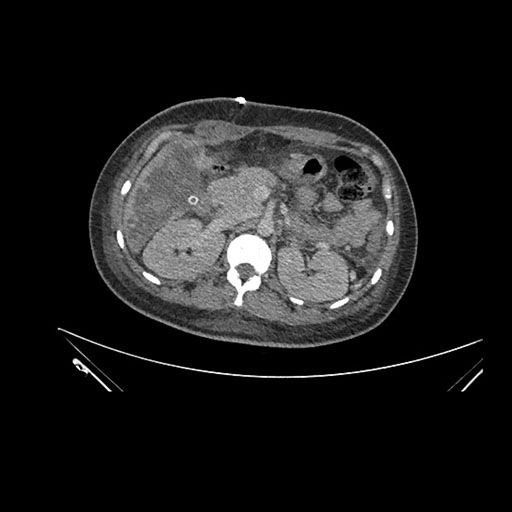

Imaging Analysis

Look through the patient's CT scan to identify any areas of concern for the necessary procedure.

Axial Arterial

Axial Venous

Based on initial findings, which issue(s) would you be most concerned about?